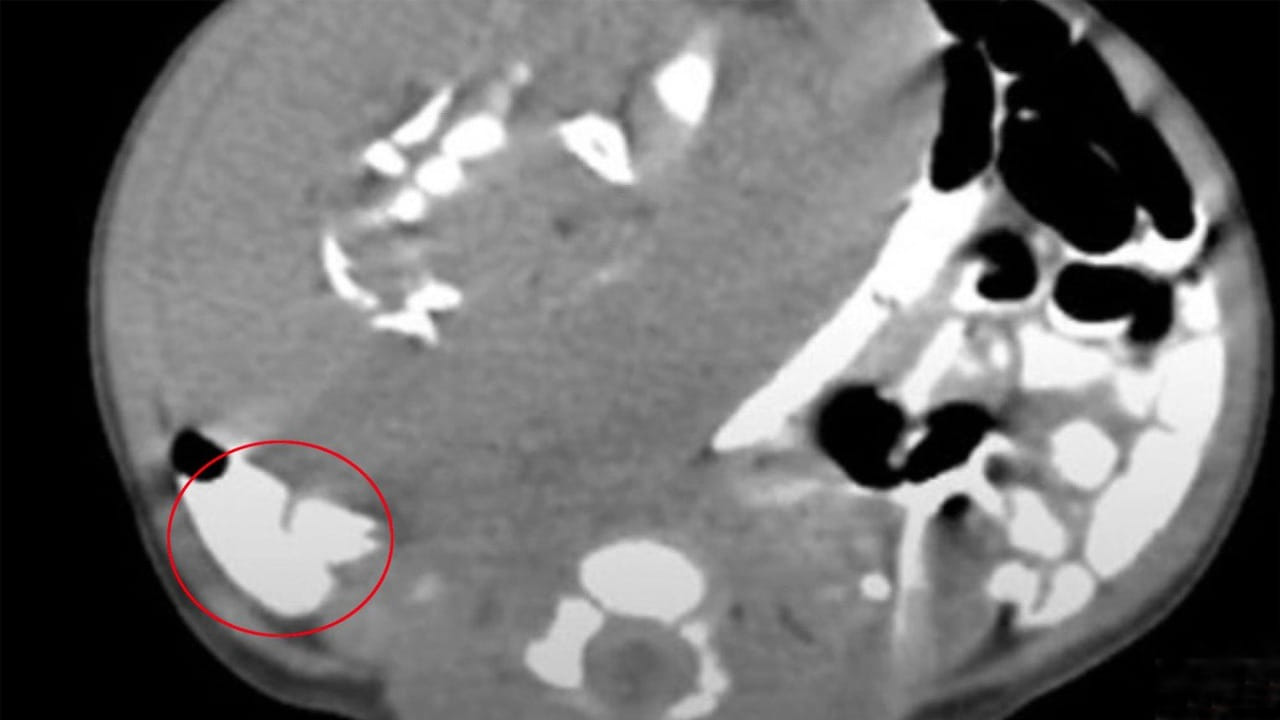

అప్పుడే పుట్టిన నవజాత శిశువు గర్భంలో పరాన్నజీవి కవల పిల్లలు పెరుగుతున్నట్లు వైద్యులు గుర్తించి గట్టి షాక్ తిన్నారు. ఆ ఆడబిడ్డ 11 రోజుల వయసులోనే ఆస్పత్రిలో చేరింది. ఆమె కడుపు ఉబ్బిపోయి.. పరిమాణం భారీగా పెరుగుతుండటంతో కుటుంబ సభ్యులు తీవ్రంగా ఆందోళన చెందారు. డాక్టర్లు వెంటనే అల్ట్రాసౌండ్ చేయగా 8*6 సెంటీమీటర్ల పరిమాణంలో ఉన్న ఓ ముద్దను కనుగొన్నారు. ఆ ముద్ద మృదువుగా.. అలాగే స్థిరంగా పెరుగుతుండటం గమనించారు. అలాగే పాప ఊపిరి తీసుకుంటున్న సమయంలో అది అస్సలు కదల్లేదని గుర్తించారు. డౌట్ వచ్చిన డాక్టర్లకు మరోసారి కాంట్రాస్ట్-ఎన్హాన్స్డ్ కంప్యూటెడ్ టోమోగ్రఫీ స్కాన్ తీయగా.. ఈసారి పొడవైన ఎముకలు, పక్కటెముకలు, వెన్నుపూస, కటి ఎముకలు, మృదు కణజాలాలను పోలి ఉండే వికృతమైన అస్థిపంజర ఆకారాన్ని చూపించింది.

వైద్యులు దానిని పిండంలో పిండం పెరుగుతున్నట్టుగా నిర్ధారించడమే కాకుండా.. ఇది చాలా అరుదు అని అన్నారు. శరీరం లోపల వికృతమైన పరాన్నజీవి కవలలు అభివృద్ధి చెందినప్పుడు సంభవించే చాలా అరుదైన క్రమరాహిత్యంగా గుర్తించారు. శస్త్రచికిత్స నిర్వహించి.. సుమారు రెండు గంటల అనంతరం వికృతమైన ఆ ఆకారాన్ని డాక్టర్లు తొలగించారు. మైక్రోస్కోపిక్ పరీక్ష ద్వారా దానిని ‘పరిణతి చెందిన పిండ కణజాలం’ ఉందని.. చర్మం, ప్రేగులు కూడా ఉన్నాయని డాక్టర్లు తేల్చారు. ఆశ్చర్యమేమిటంటే.. ఆ పాపకు ఎలాంటి లక్షణాలు కనబడలేదు. బాగానే తిన్నది అని అన్నారు. ఆసుపత్రిలో చేరిన నాలుగు రోజుల తర్వాత ఆ పాప కడుపులోంచి ఆ ముద్దను తొలగించారు. అసాధ్యమైన రీతిలో ఆమెను ఆపై ఆరోగ్యవంతంగా డిశ్చార్జ్ చేశారు. ఈజిప్టులోని మన్సౌరా యూనివర్సిటీ పీడియాట్రిక్ విభాగంలో చికిత్స పొందిన ఈ పాప గురించి అక్టోబర్ మెడికల్ జర్నల్లో పొందుపరిచారు.